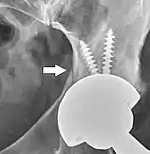

Loosening

Hip prosthesis displaying aseptic loosening (arrows)

Hip prosthesis zones according to DeLee and Charnley,[29] and Gruen.[30] These are used to describe the location of for example areas of loosening.

On radiography, it is normal to see thin radiolucent areas of less than 2 mm around hip prosthesis components, or between a cement mantle and bone. These may indicate loosening of the prosthesis if they are new or changing, while areas greater than 2 mm may be harmless if they are stable.[31] The most important prognostic factors of cemented cups are absence of radiolucent lines in DeLee and Charnley zone I, as well as adequate cement mantle thickness.[32] In the first year after insertion of uncemented femoral stems, it is normal to have mild subsidence (less than 10 mm).[31] The direct anterior approach has been shown to itself be a risk factor for early femoral component loosening.[33][34][35]